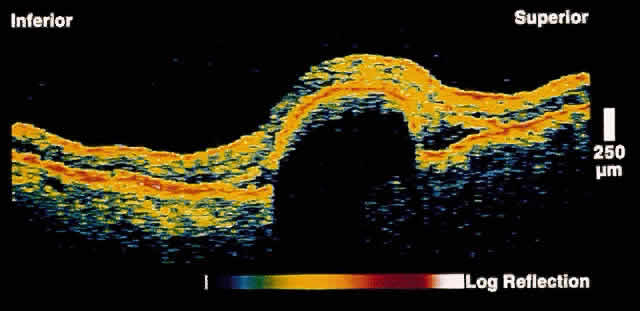

RETINA Central Serous Chorioretinopathy Central serous chorioretinopathy (CSCR) is characterized by detachment(s) of the neurosensory retina caused by one or more focal leaks at the level of the RPE. When small or shallow, these serous detachments may be difficult to detect clinically. OCT images of such areas demonstrate elevation of neurosensory retina by the presence of subretinal fluid.12 The well-defined contrast in optical reflectivity between the nonreflective serous fluid and the more highly reflective posterior boundary of the neurosensory retina allows OCT images to be highly sensitive to even small neurosensory detachments. Indeed, OCT images may show the presence of neurosensory detachments not detectable by clinical examination. The ability of OCT to image the same retinal area on subsequent visits allows for the longitudinal monitoring of the clinical course of the serous detachment in this disease (Figs. 2 and 3). OCT is particularly useful when thisdisease presents in older patients. The presence of drusen and pigmentary changes in these patients may lead to the erroneous conclusion that a choroidal neovascular complex is the cause of the neurosensory detachment. OCT may be able to provide additional diagnostic information in these patients by excluding the existence of a choroidal neovascular membrane or abnormalities in the choriocapillaris/RPE layer.